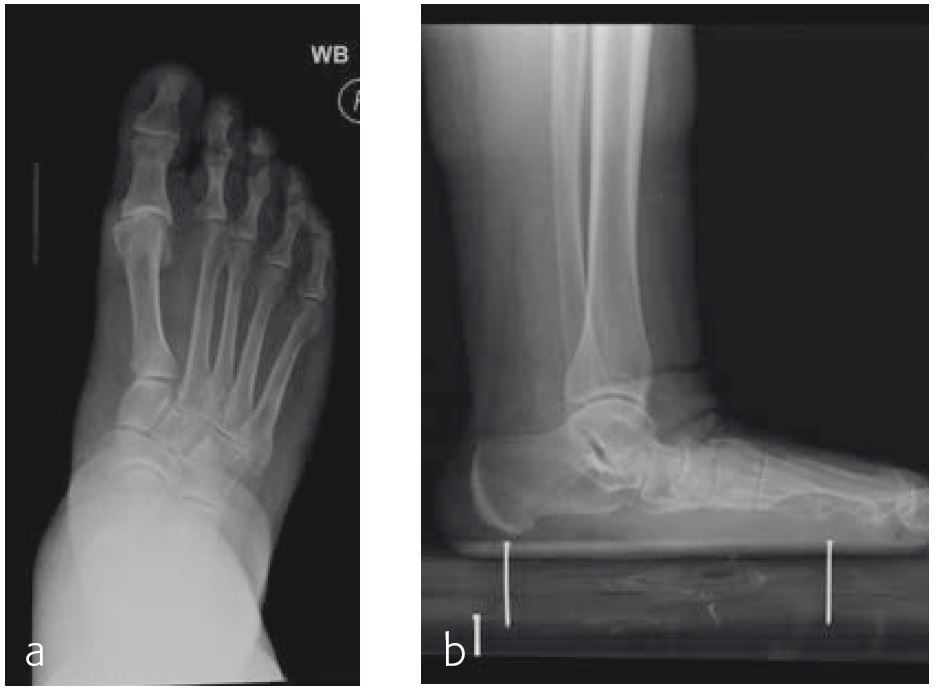

Case 2: 70-year-old patient

A 70-year-old female patient (Fig 1) had a long history of increasing painful deformity of her foot. She also noted increasing gait problems. There was no history of initial trauma. The examination showed severe rigid flatfoot deformity.

An extended triple arthrodesis was performed. Medially, the new Medial Column Plate was used, securing the talonavicular, naviculocuneiform, and tarsometatarsal joints (Fig 2). The X-plate is lateral and secured the calcaneo-cuboid joint. Two 7.3 mm screws were used to secure the subtalar joint.